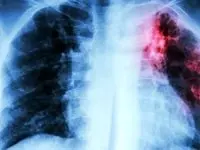

کشندهترین بیماری عفونی جهان معرفی شدبه گفته سازمان بهداشت جهانی، ۱.۲۳ میلیون نفر در سال گذشته میلادی بر اثر این بیماری عفونی جان باختند.